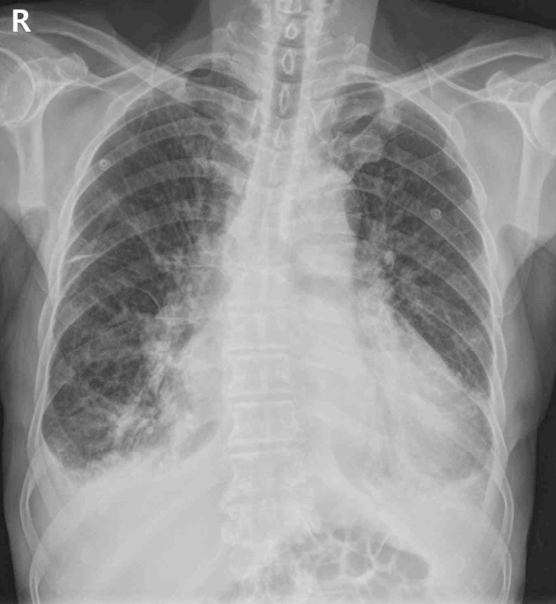

48세 남자가 3일 전부터 숨이 차서 병원에 왔다. 혈압 120/82 mmHg, 맥박 61회/분, 호흡 20회/분, 체온 36°C이다. 맥박은 규칙적이나 제3심음과 말굽심음이 들리고 양쪽 등아랫부분에서 거품소리가 들린다. 가슴 X선사진과 심전도이다. 검사 결과는 다음과 같다. 치료는?

CXR: Cardiomegaly, pulmonary edema, bilateral pleural effusion

3일 만에 악화된 호흡곤란과 BNP 상승, 심초음파 상 LVEF의 감소, CXR에서 pulmonary edema 소견을 통해 급성 비보상성 심부전으로 진단하고 호흡곤란 증상 개선을 위해 loop diuretics인 퓨로세마이드를 투여한다.

• CXR에서 cardiomegaly와 함께 혈액검사에서 BNP의 상승을 보이므로 HF일 가능성이 높다.

• CXR에서 pulmonary edema가 확인되므로 체액 저류가 현저하며, 급성 호흡곤란 증상이 나타난다. 이는 심장 기능 이상에 의한 것으로 ADHF로 진단할 수 있다.